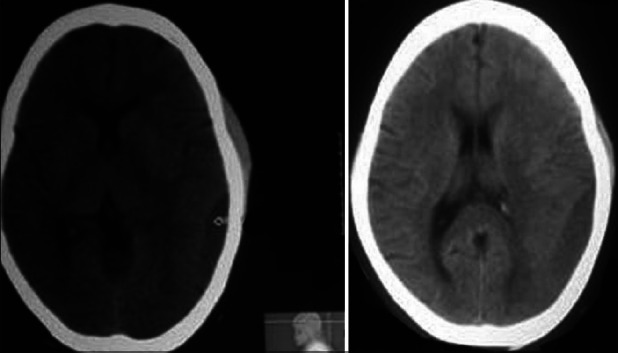

Intracranial hemorrhage is a rare devastating complication of idiopathic thrombocytopenic purpura (ITP), mostly presenting as intraparenchymal or subarachnoid haemorrhage. Isolated chronic subdural haematoma (SDH) is still very rare and the optimal management is unsettled. Spontaneous resolution of chronic SDH in patients with idiopathic thrombocytopenic purpura is possible. We report a case of spontaneous chronic SDH in a patient with ITP with hemiparesis where the haematoma significantly decreased in size with complete resolution of hemiparesis as a result of platelet transfusions and continuing therapy with steroids. Surgical treatment of subdural haematoma with consequent bleeding complications can be avoided in this scenario.